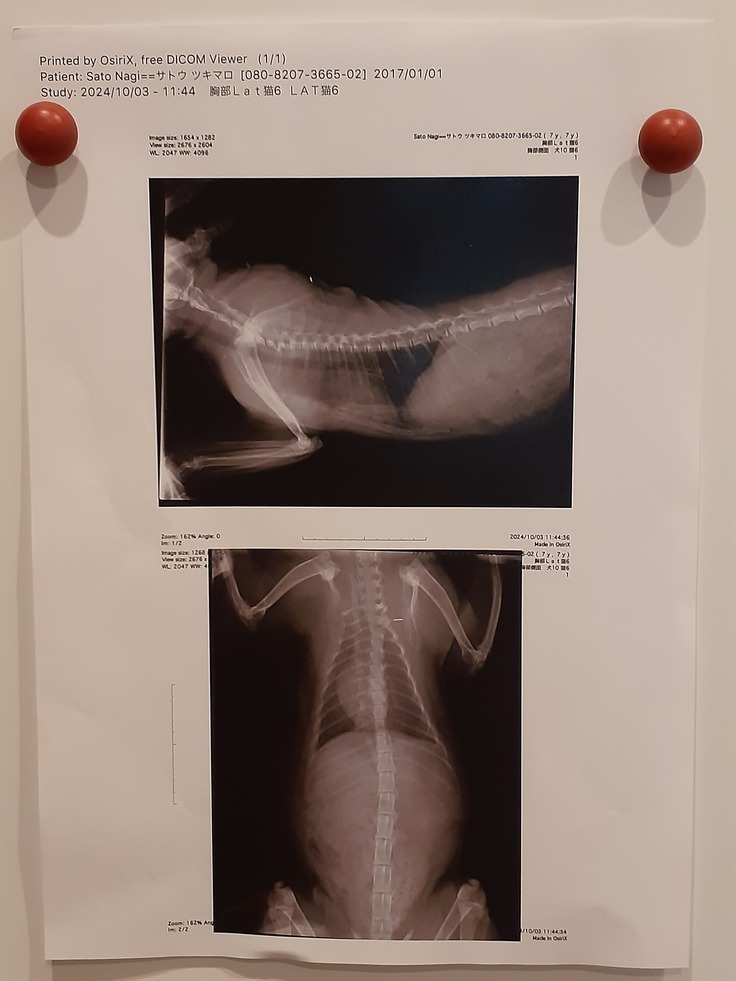

そしてレントゲンの脊椎など綺麗だったこと。

これも足の麻痺などとは関係なく、ウサギ足については大脳低形成にある筋力の低下に当てはまるということです。